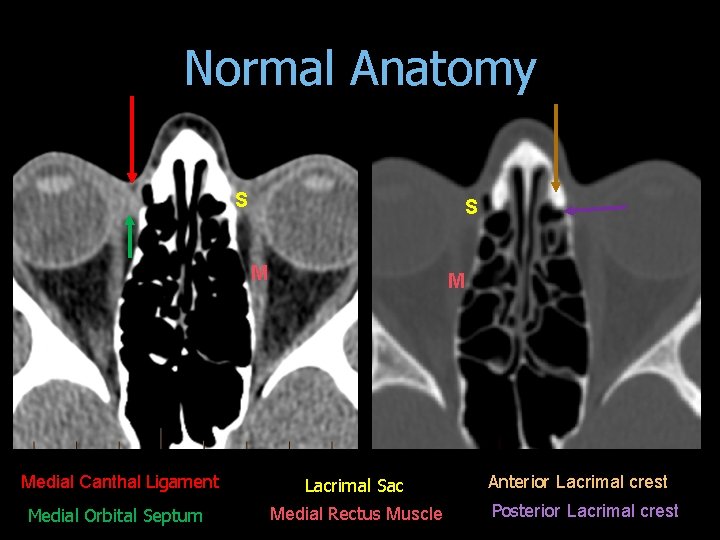

Normal Anatomy S S M Medial Canthal Ligament Medial Orbital Septum M Lacrimal Sac Medial Rectus Muscle Anterior Lacrimal crest Posterior Lacrimal crest